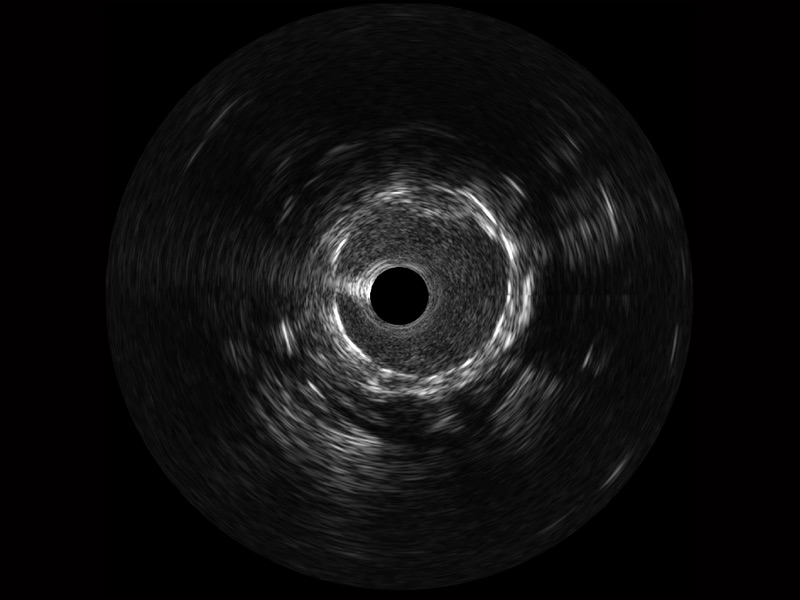

传统IVUS图像

对比传统IVUS导管成像,云顶集团官网宽频IVUS图像的近场支架梁显影更细腻,远场中膜外血管仍清晰可辨,兼顾远中近,兼顾分辨力与穿透深度